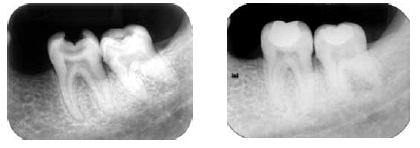

Julgue os itens a seguir acerca das radiografias acima, que mostram a preservação, após dois anos de um tratamento.

As imagens não apresentam falhas associadas ao tratamento de restauração realizado.

A câmara pulpar do dente 38 reduziu de tamanho.

Provas

É possível observar que os nódulos de calcificação pulpar do dente 37 estão progredindo.